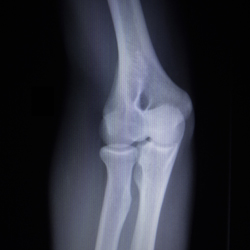

Knochen

CT

Frakturen

• Beurteilung Fragmentstellung (präoperativ und Verlaufskontrolle, Frakturdurchbau)

Gelenke

Sämtliche Gelenke mit der Abklärung knöcherner Veränderungen